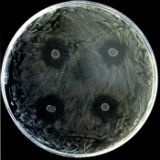

Unas bacterias presentes en la cavidad oral pueden proteger de la caries

La caries es la enfermedad infecciosa más común en todo el mundo y, aunque está condicionada por múltiples factores, estudios recientes han identificado unas bacterias en la cavidad oral que protegen frente...